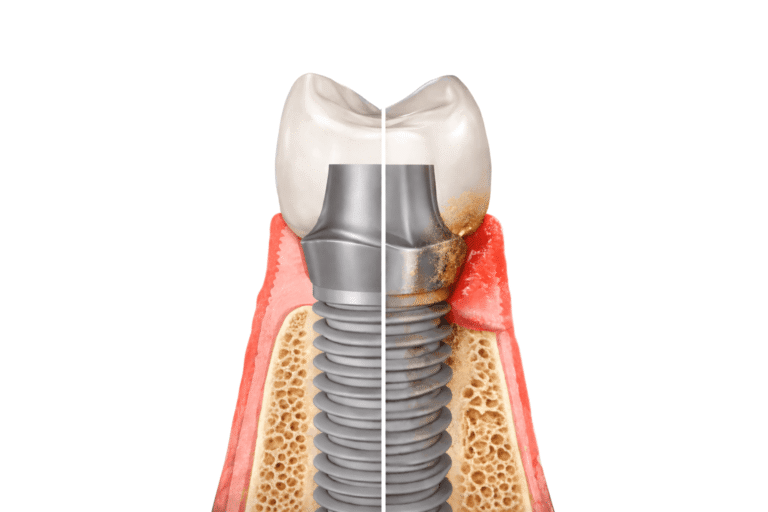

La perimplantite è una delle complicanze più rilevanti in implantologia. Si tratta di un processo infiammatorio che interessa sia la gengiva sia l’osso attorno all’impianto e che, se non trattato, può comprometterne la stabilità.

La perimplantite è una patologia infiammatoria che colpisce i tessuti attorno a un impianto dentale già osteointegrato. Coinvolge inizialmente la mucosa peri-implantare e, nelle fasi più avanzate, determina una progressiva perdita di osso di supporto.

È importante distinguerla dalla parodontite. Quest’ultima interessa i tessuti che sostengono il dente naturale (gengiva, legamento parodontale e osso alveolare), mentre la perimplantite riguarda i tessuti attorno a un impianto (osso), che non possiede legamento parodontale e presenta caratteristiche anatomiche differenti.

Questa differenza non è solo terminologica. I tessuti peri-implantari rispondono in modo diverso all’infiammazione rispetto a quelli che circondano un dente naturale. La progressione della perdita ossea può essere più rapida e meno evidente nelle fasi iniziali.

La perimplantite è spesso preceduta da una fase reversibile chiamata mucosite peri-implantare, in cui l’infiammazione interessa solo i tessuti molli senza perdita ossea. Se non trattata, può evolvere verso una condizione più complessa e strutturale.